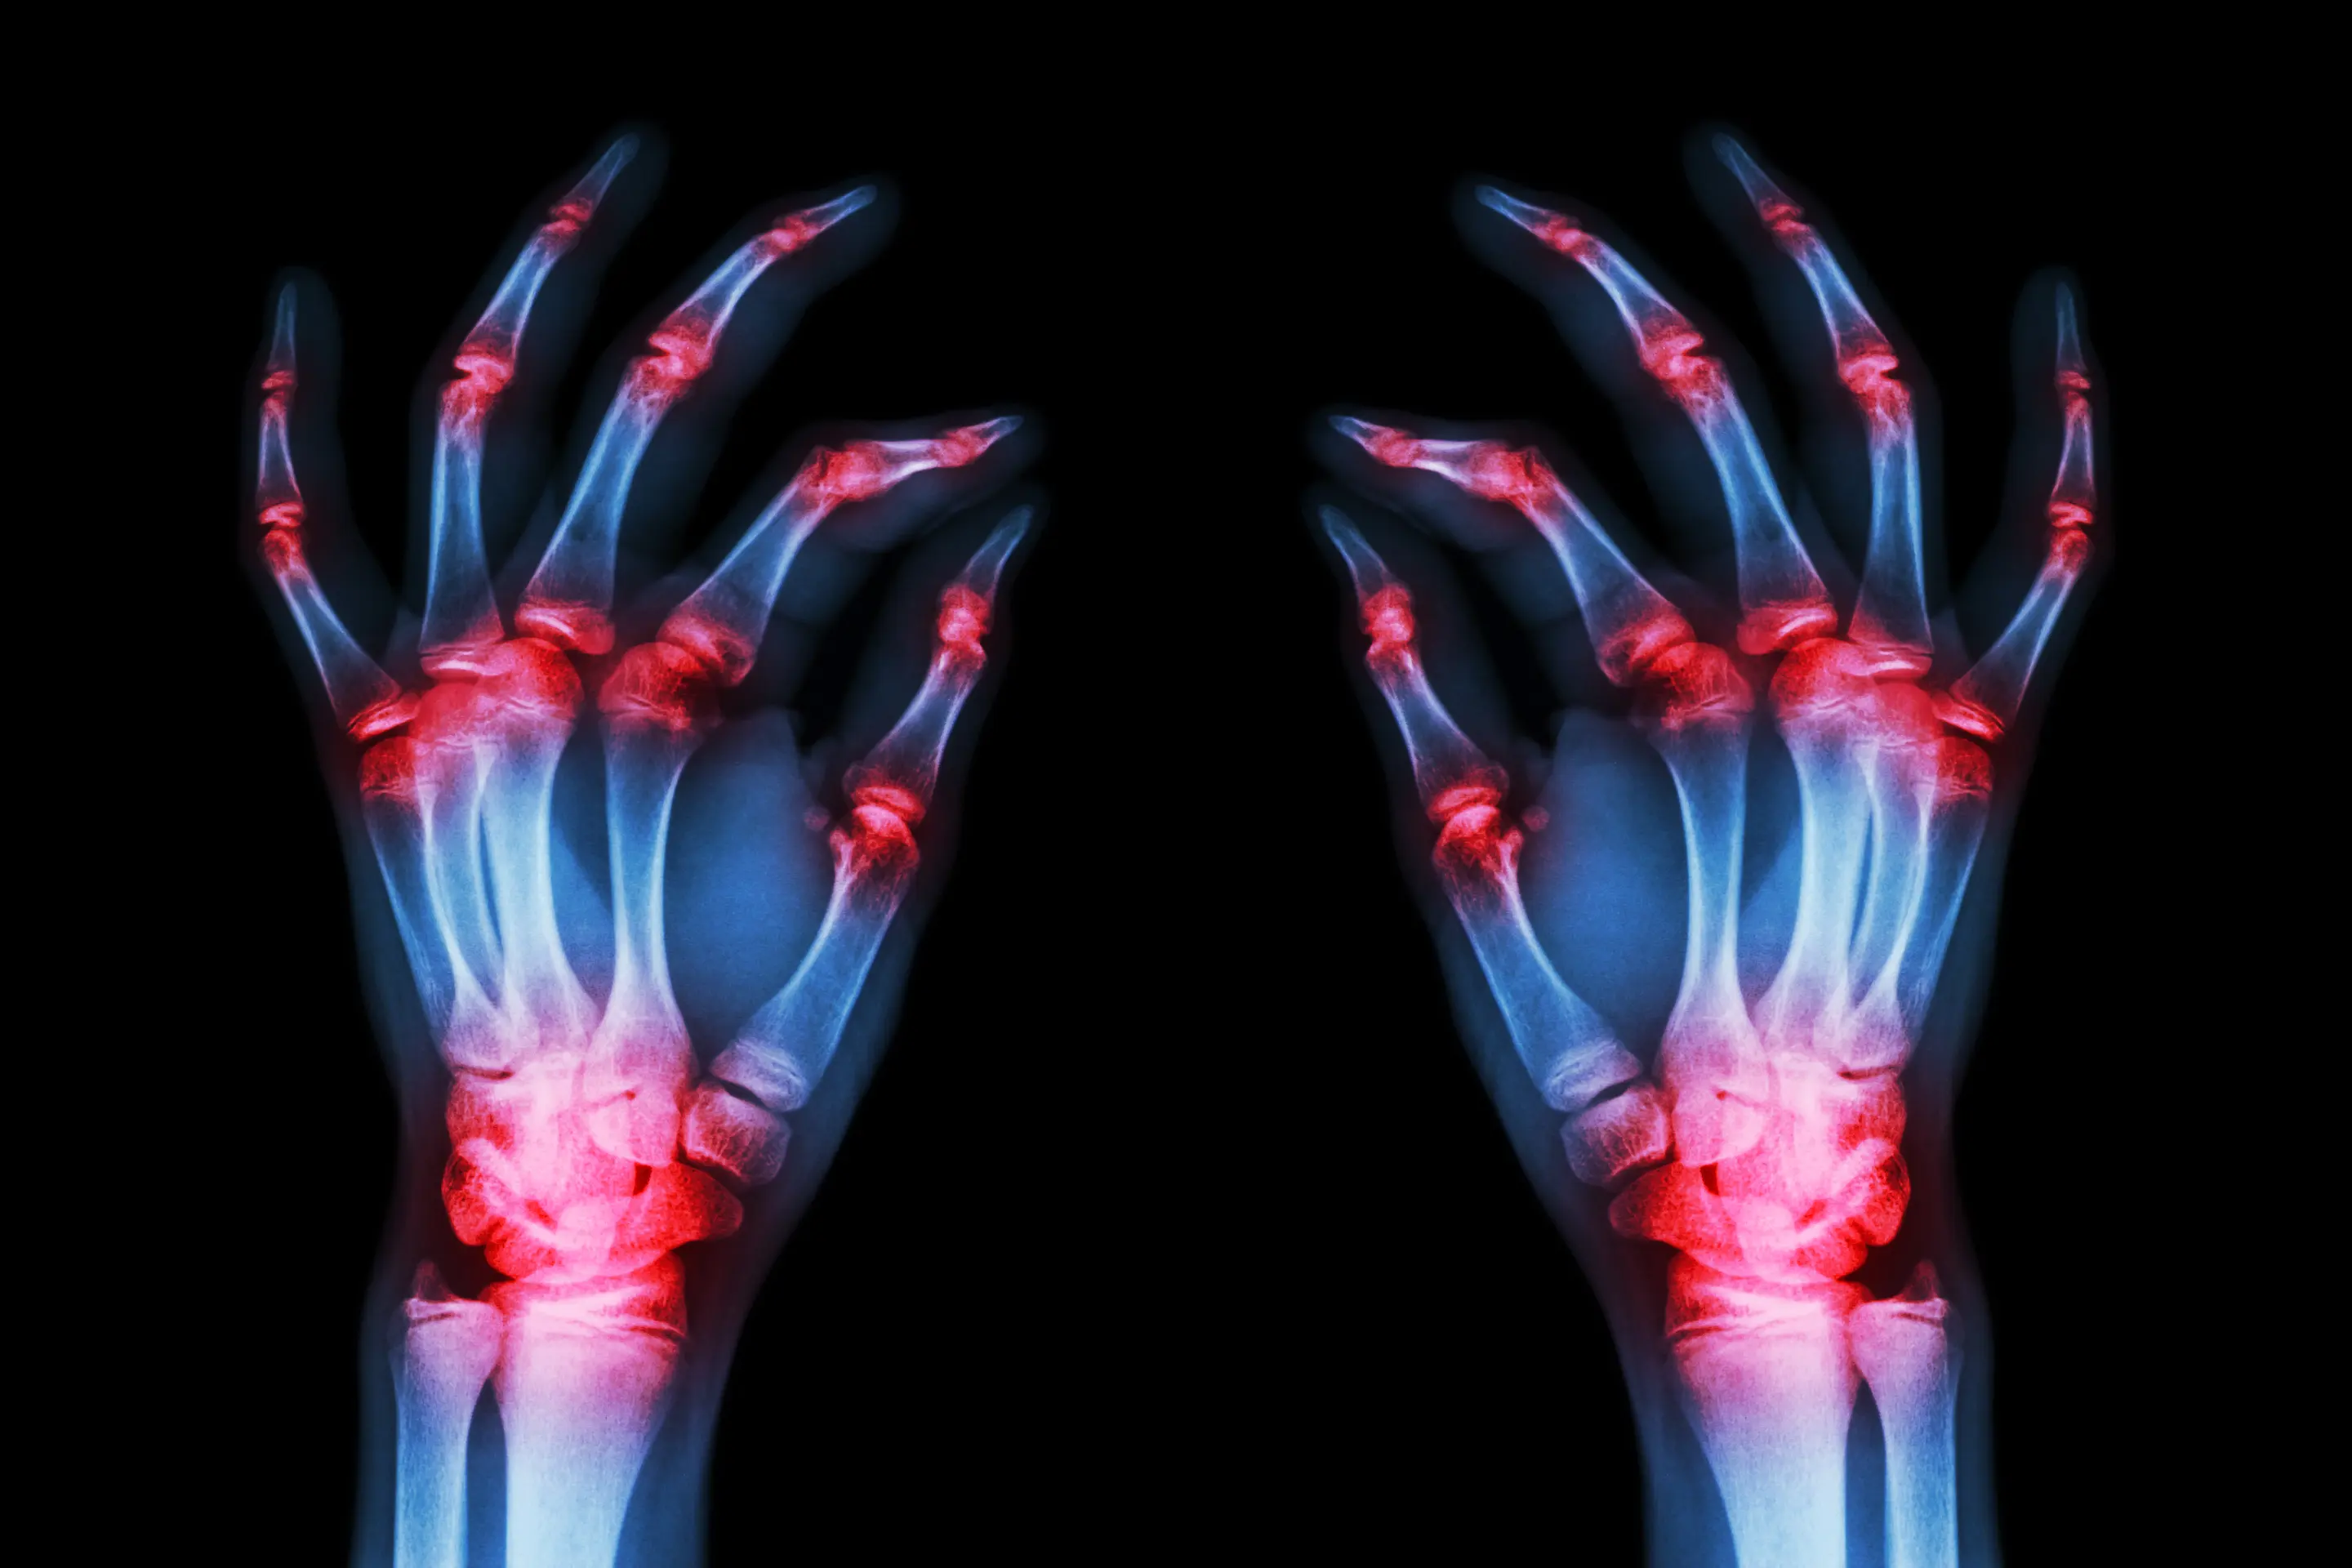

Rheumatoid arthritis is a chronic condition in which the immune system attacks the body’s own joint tissues.